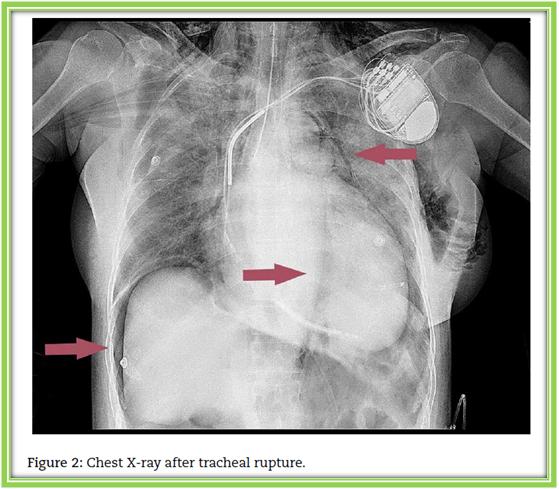

支气管镜检查证实气管近端部分破裂,即声带下方。胸部X线显示右侧膈下间隙有皮下气肿、心包气肿、纵隔气肿和气腹征象 (图2)。重新插管后,患者的呼吸系统症状稳定,根据胸外科医师的决定,患者仍在接受观察和保守治疗,无需进一步手术干预。由于心脏收缩功能下降和心包内空气迅速积聚导致血流动力学参数不稳定,静脉输注多巴酚丁胺和去甲肾上腺素维持血流动力学稳定。我们观察到炎症标志物如C反应蛋白、血沉率、白细胞的增加。对患者的血液标本进行细菌培养,之后,除了继续治疗心力衰竭外,还开始了广谱抗生素治疗(头孢曲松)以预防纵隔炎。